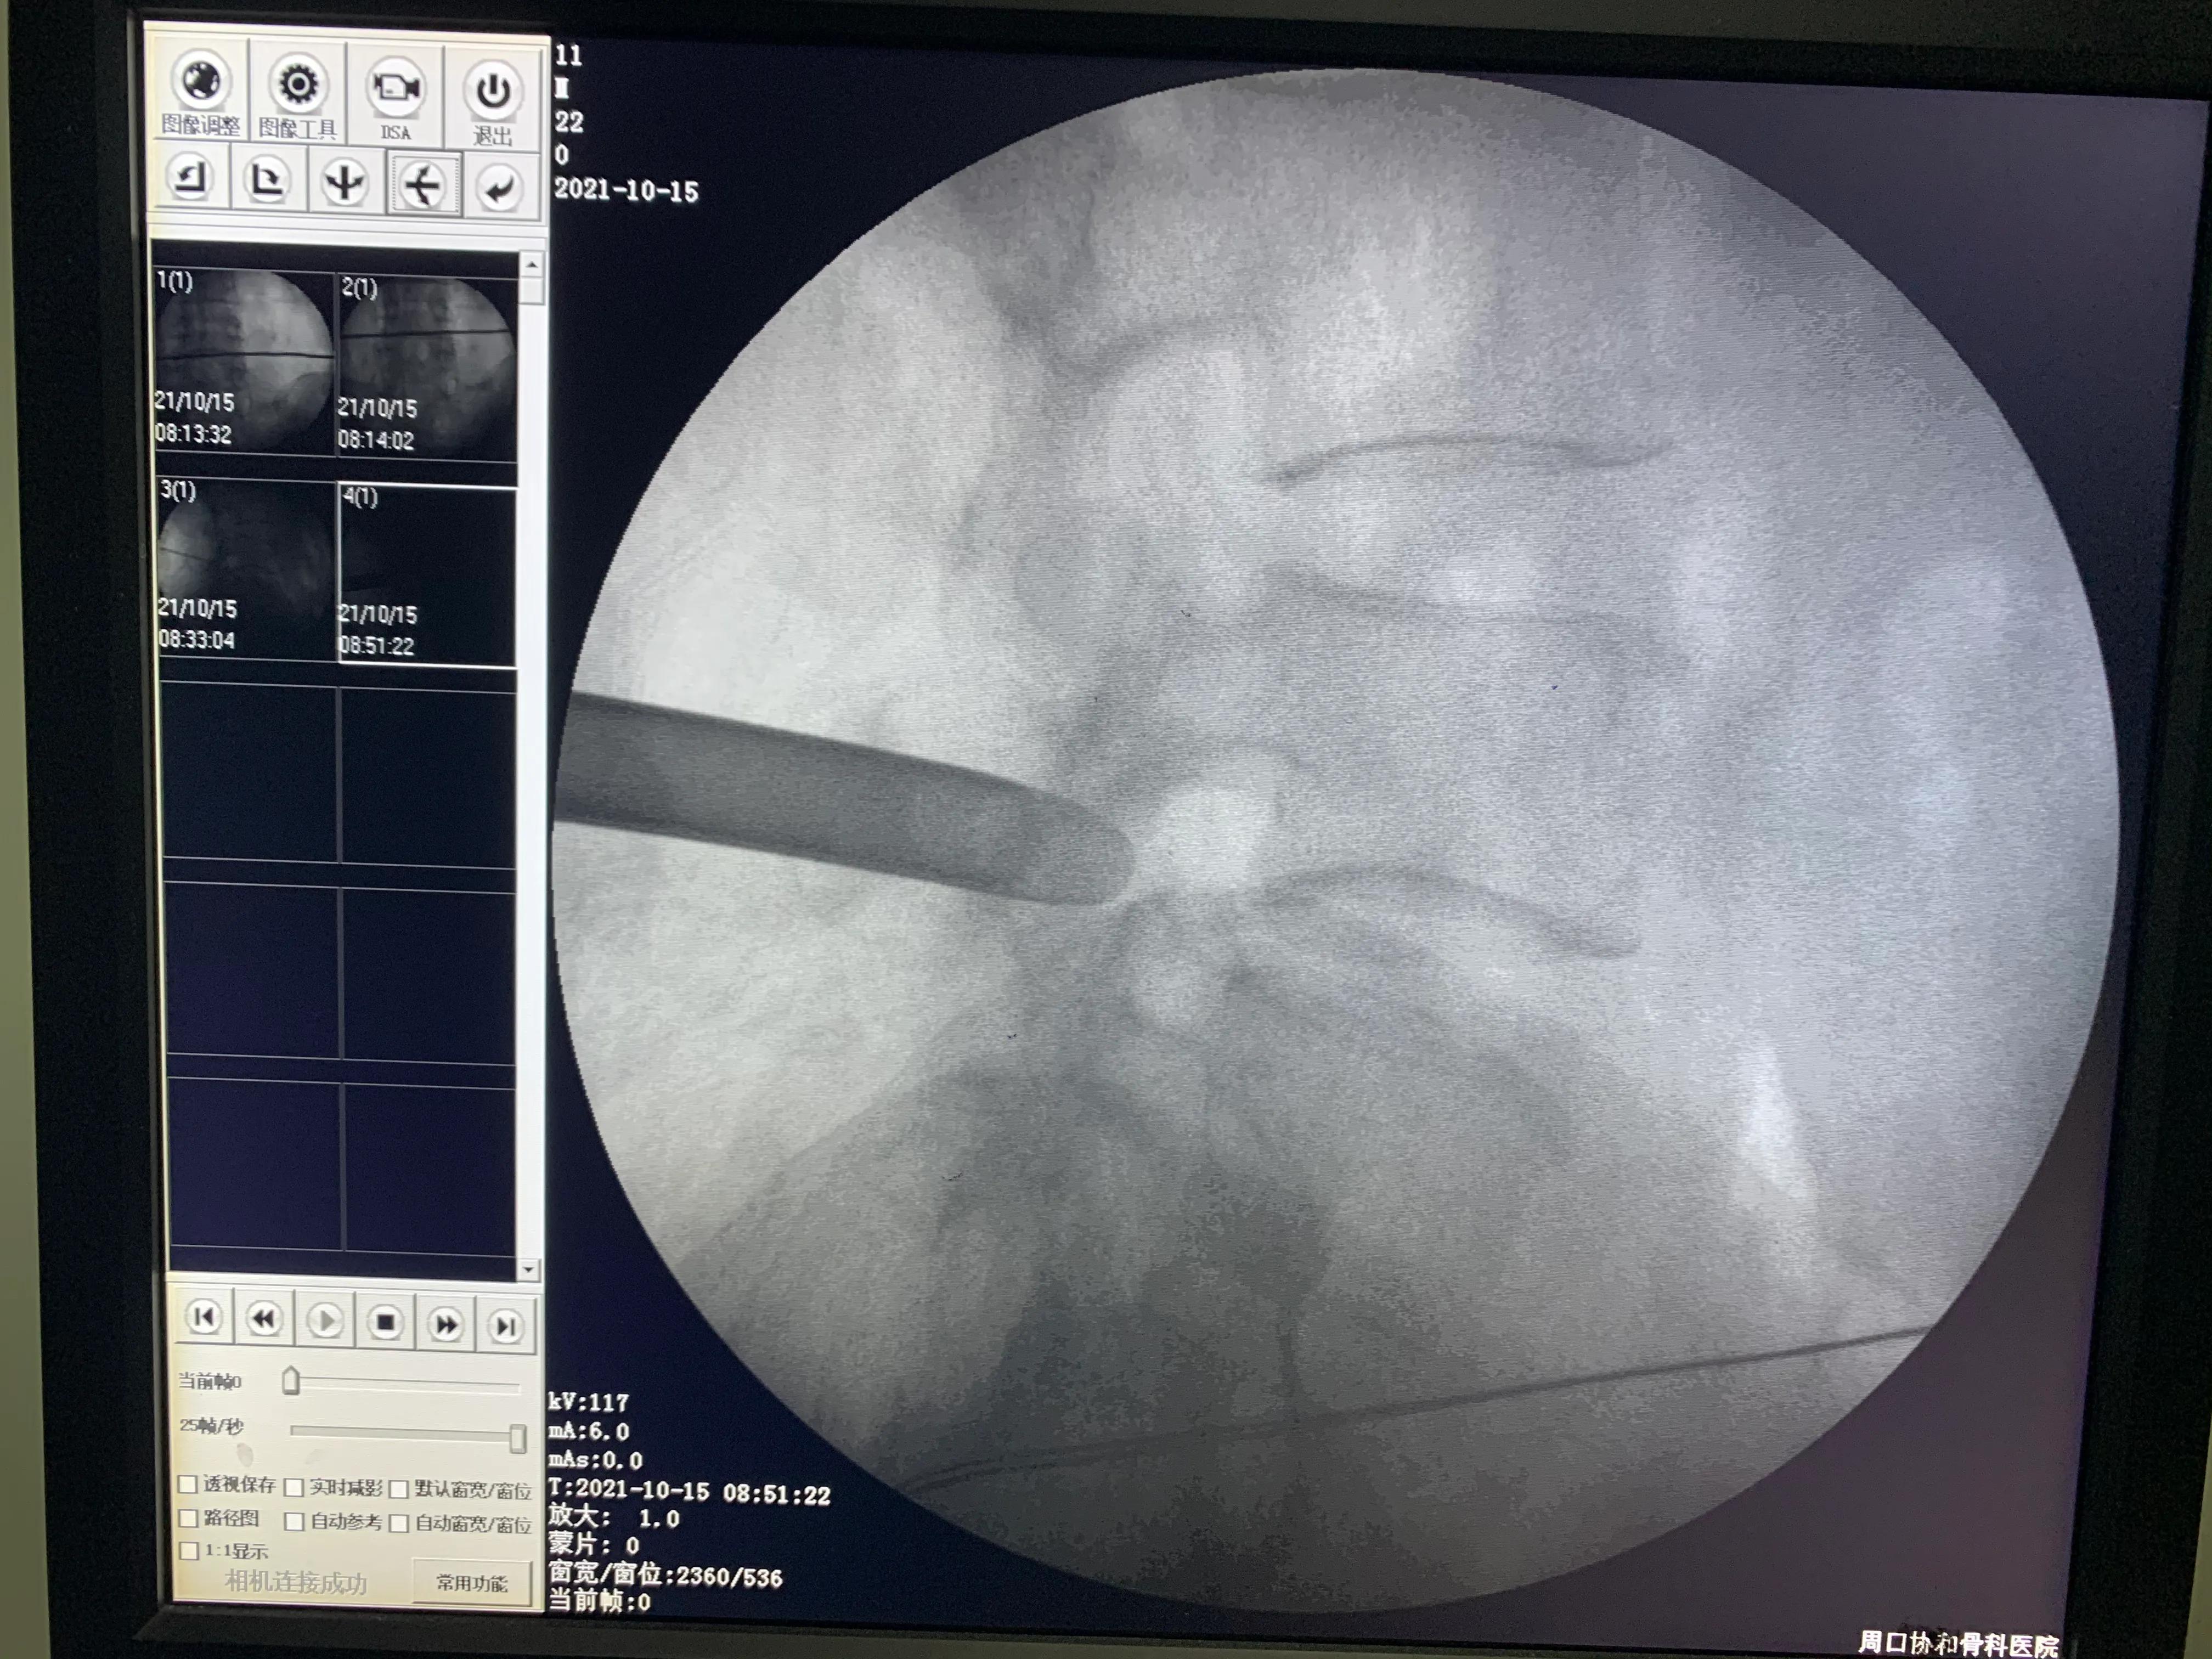

术中定位不清,一定要透视,不要盲目开口

术中透视